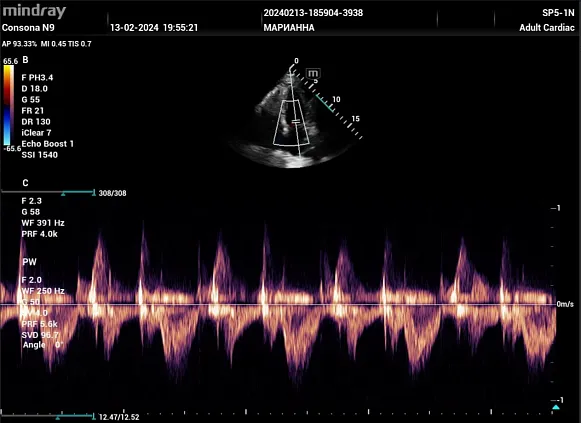

Клинические изображения

Mindray Consona N9 — это консольная ультразвуковая система премиального уровня, разработанная компанией Миндрей для комплексной диагностики. Аппарат построен на платформе ZST+ (Zone Sonography® Technology+), которая обеспечивает высокую чёткость и однородность изображения даже при сложных клинических исследованиях. Благодаря широким возможностям визуализации, Consona N9 Миндрей успешно применяется в акушерстве, гинекологии, кардиологии, абдоминальной и общей диагностике. Система относится к классу «система ультразвуковой визуализации универсальная серии Consona», что подтверждает её универсальность и высокую клиническую ценность.

Функциональные возможности аппарата включают целый комплекс интеллектуальных решений: Smart OB, Smart Face, Smart Pelvic, Smart Planes CNS, AutoEF, Smart Bladder, HD Scope, HR Flow и Sound Touch Elastography. Эти технологии помогают врачу быстрее получать точные результаты, автоматизировать рутинные измерения и снизить нагрузку на персонал. Такой подход делает УЗИ аппарат Consona N9 надёжным инструментом как для рутинных осмотров, так и для экспертных исследований. По отзывам специалистов, УЗИ аппарат Mindray Consona N9 Миндрей обеспечивает высокую стабильность и точность диагностики на уровне лучших мировых систем.

- Кардиология и сосуды;